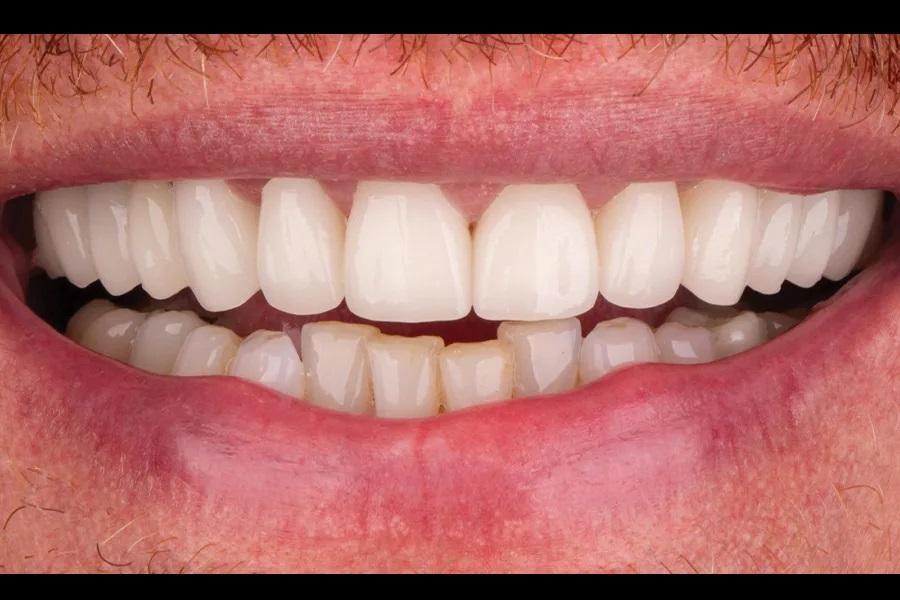

При реабилитации одной дуги точный диагноз и понимание ожиданий пациента критически важны для составления плана. После верификации ОЖП окклюзию необходимо было скорректировать для долговечности реставраций. Возможен был ортодонтический подход (увеличение ВРО за счет экструзии моляров одной из дуг, интрузии 3.3–3.2–3.1–4.1–4.2 и/или прогнатизации 1.2–2.2), но пациент категорически отказался от ортодонтии. Поскольку верхние зубы имели крупные дефектные реставрации и были структурно ослаблены, полноокрывающие коронки на весь верхний ряд стали разумным решением: они поддерживали ослабленные зубы (снижение биомеханического риска), увеличивали ВРО для коррекции ОЖП и обеспечивали желаемую эстетику (Фото 14 – Фото 17).

Фото 15. Улыбка после лечения, крупный план.

Фото 17. Полная улыбка после лечения.